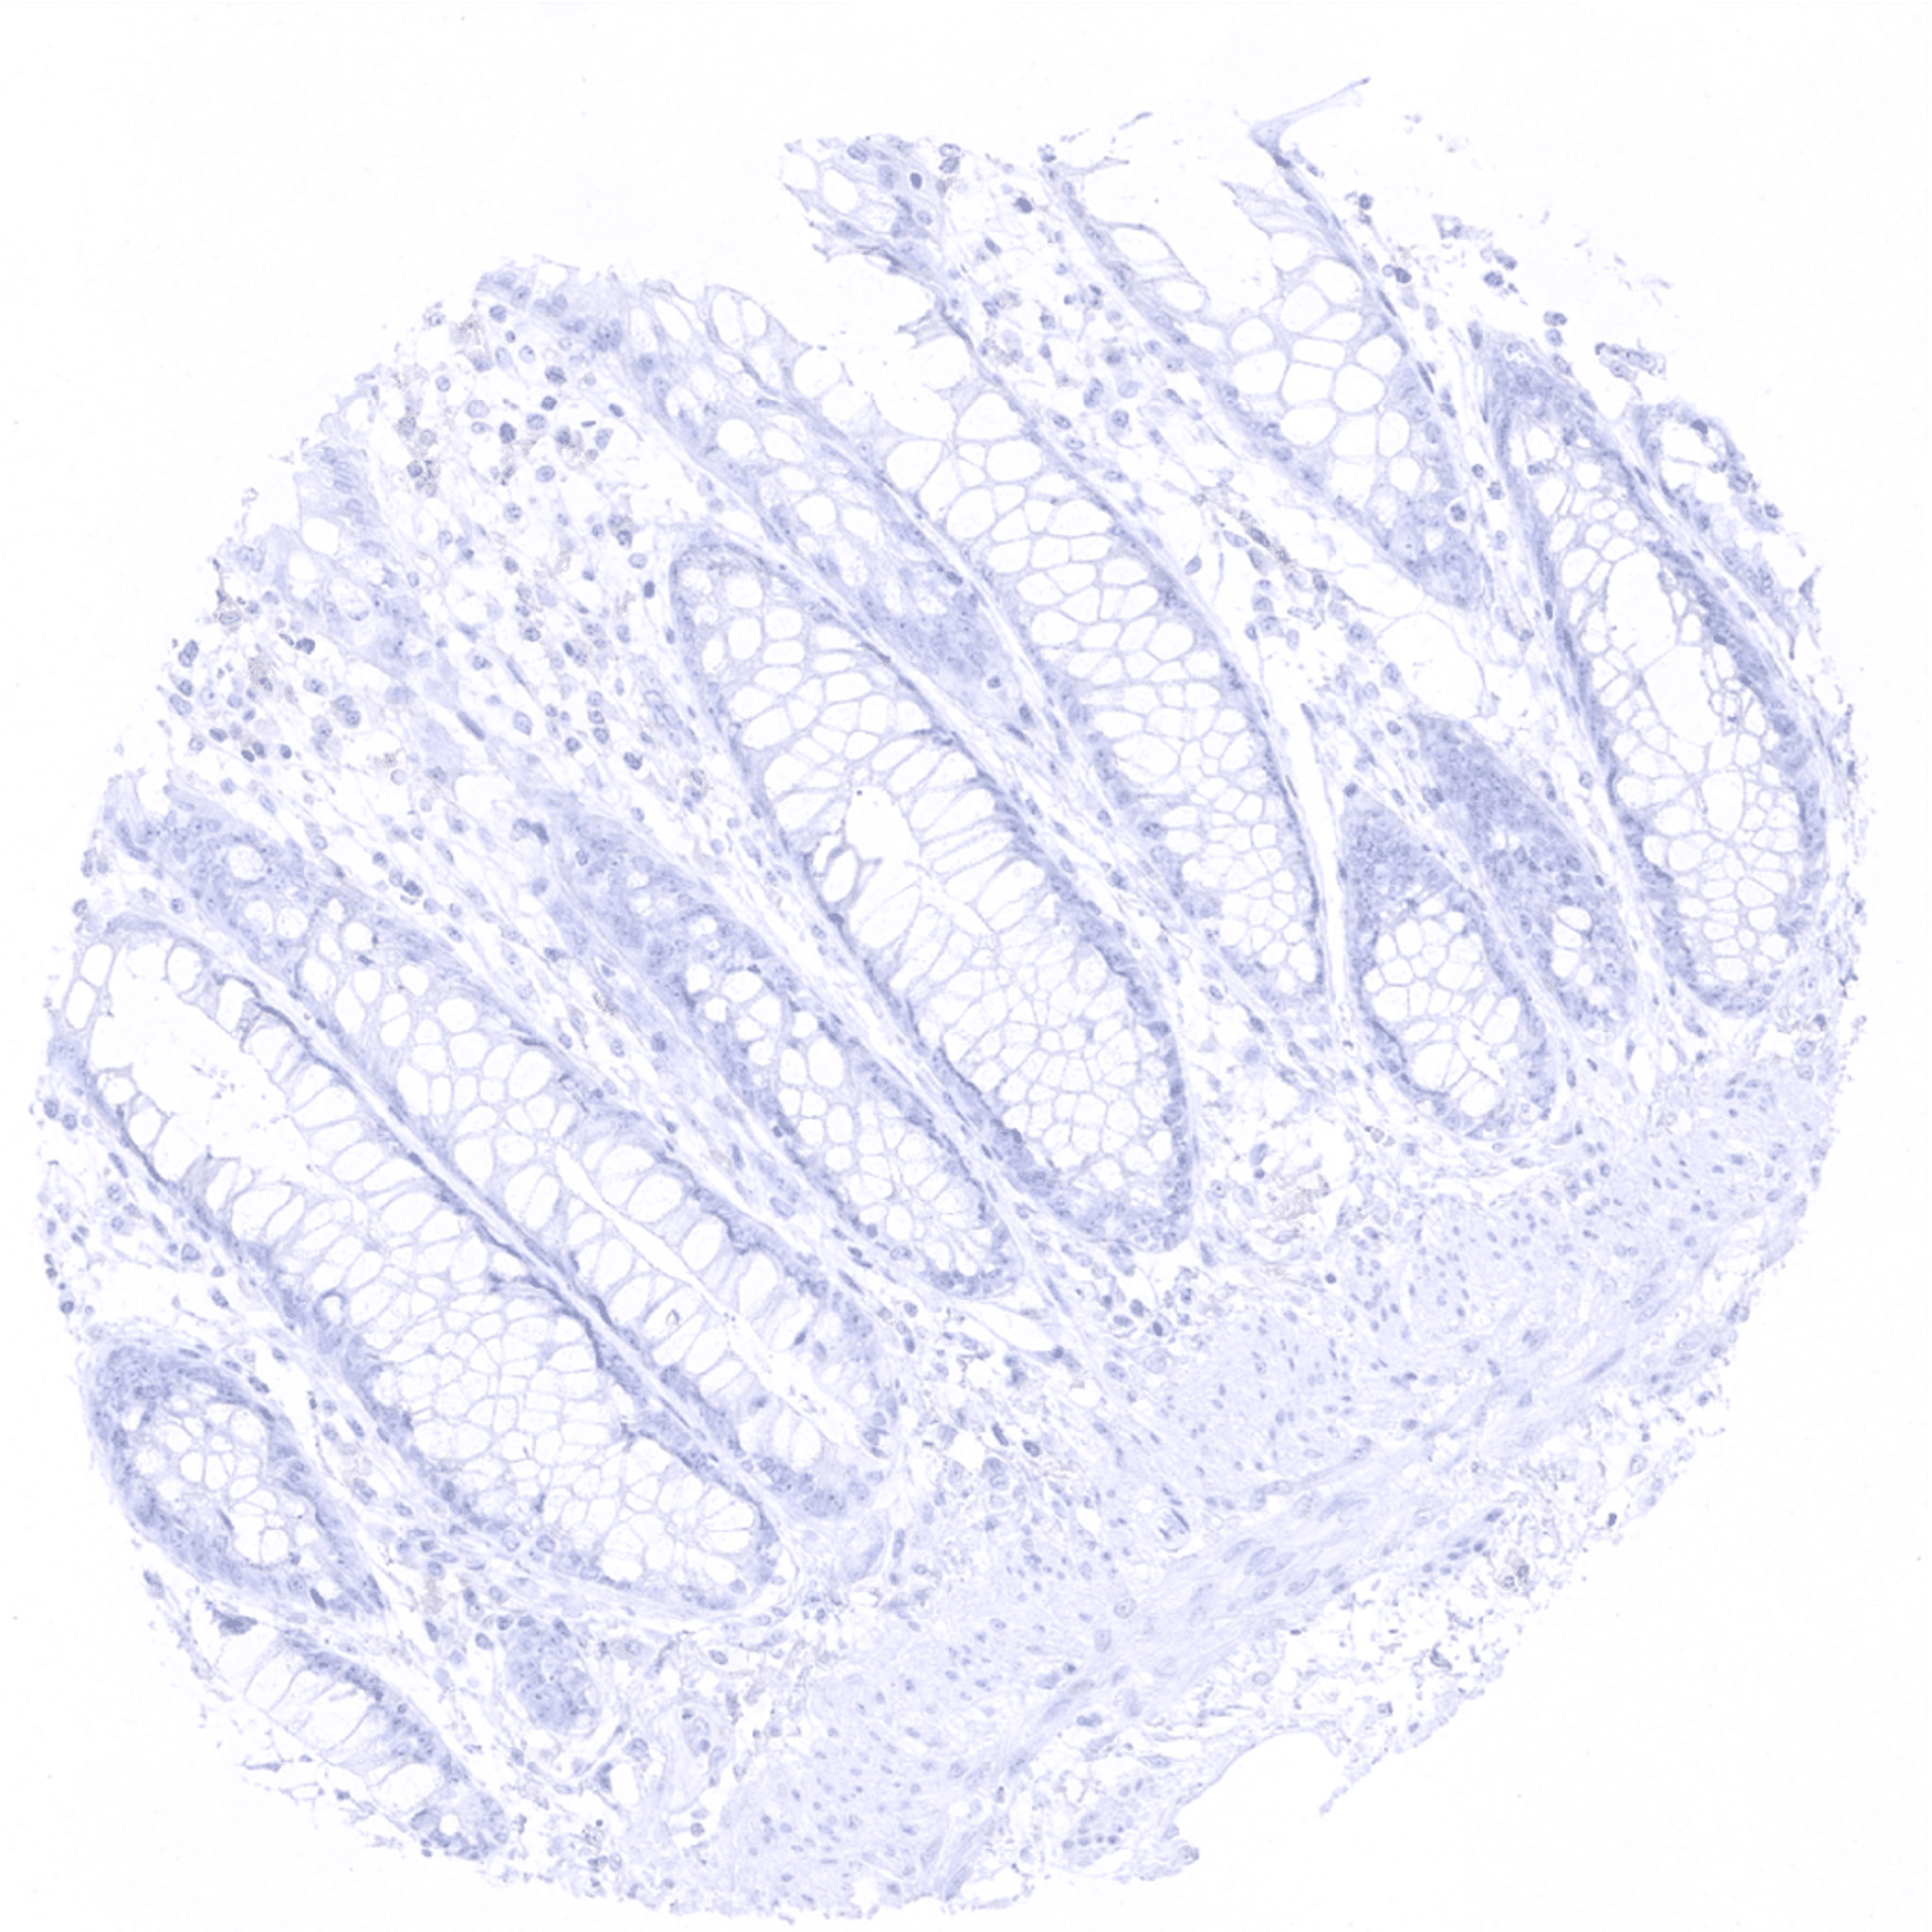

colon descendens, mucosa

colon descendens, muscular wall